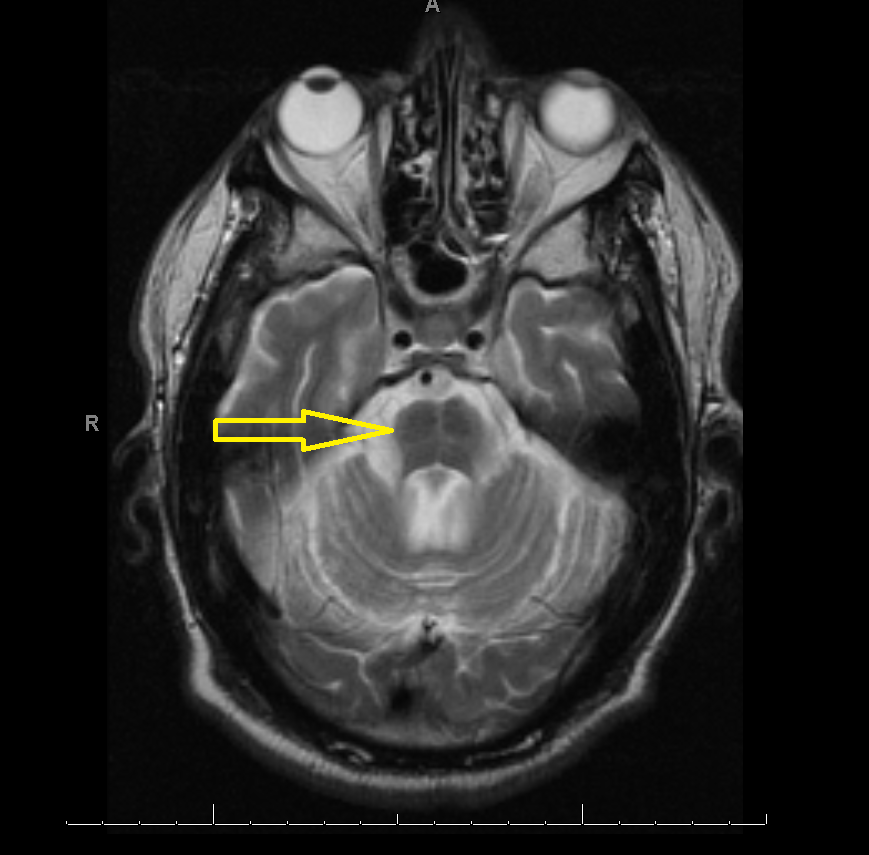

Middle age male patient admitted for evaluation of syncope. He has a history of coronary artery disease, severe pulmonary HTN, COPD, anemia of chronic disease, Osteoarthritis, left vocal cord paralysis, orthostatic hypotension, unsteady gaits and previous syncopal episode. CT head imaging remarkable for cerebellar atrophy. MRI done showed moderate cerebellar atrophy, midbrain atrophy with hummingbird sign and hot cross bun sign in the pons representing neurodegenerative disease multisystem atrophy and progressive supranuclear palsy.

Magnetic Resonance Imaging (MRI) is the modality of choice – atrophy of putamen, middle cerebellar peduncle, or pons on MRI is supportive for possible MSA. MRI radiographic features include hot cross bun sign, atrophy of cerebellum and midbrain, putaminal rim  sign.